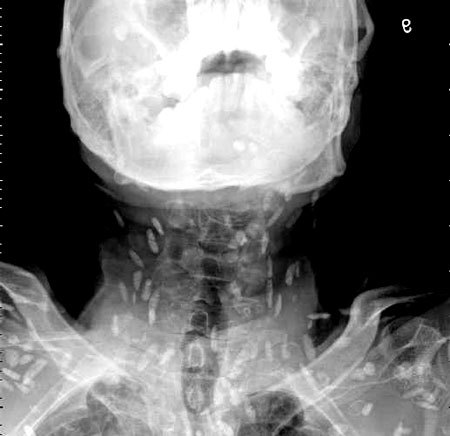

광둥성 푸산시 순더 지역에서 한 남성은 회를 섭취한 뒤, 복부 통증과 피부 가려움증 증상을 겪었습니다. 이로 인해 그는 난팡 의과대학 부속병원을 찾아 진료를 받았습니다. 의사는 이 환자의 증상을 확인하기 위해 엑스레이를 촬영하였고, 이 사진에서는 그의 온몸에 기생충이 퍼져 있는 것을 확인할 수 있었습니다. 이러한 기생충은 촌충 또는 열두 조충이라고 불리는 벌레로서, 사람의 장내에서 기생하는 것으로 알려져 있습니다.